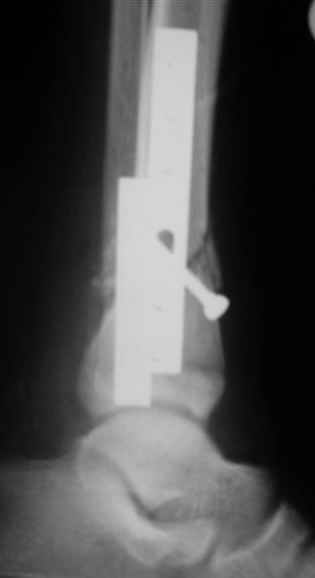

Уважаемые коллеги,Больной 17 лет , 3 недели с момента травмы, был переведен в наше отделение из соседнегогоспиталя.

Попытка закрытой ручной репозиции, предпринятая ранее в этой больнице,оказалась безуспешной, что и явилось причиной перевода к нам.Чтобы вы предложили в данной ситуации?Показана ли фиксация перелома малоберцовой кости в данном случае или в этом нет необходимости?Евгений Чекашкин

АВФ -отдельная история в нашем краю, поэтому последний вариант -открытая репозиция, что я и сделал: Без мобилизации отломков б.б. репозиция м.б. не получалась. Первым делом фиксировал перелом м.б. кости пластиной на 4 4,5 мм винтах,

при ревизии зоны перелома б.б. кости сохранялось смещение дистального отломка кпереди, пришлось принять меры и решить эту проблему.

На прямой проекции видно угловое смещение отломков малоберцовой кости, обуславливающий и

наклон тарана, да и вальгус отломков б.б. , а на боковой проекции -смещение отломков

кпереди и по длине.